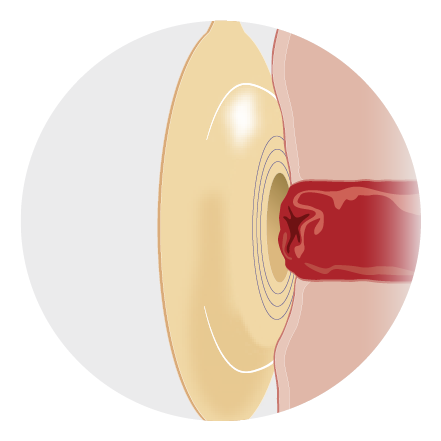

How convexity pouch systems work with a flush or retracted stoma¹

1.Position theskin barrier above a flushstoma. This also works with retracted stomas or with skin folds. |

2.The convex skin barrier exerts downwards pressure on the skin. |

3.The pressure on the peristomal skin will help the stoma protrude further into the pouch, allowing for a better seal and helping to. |